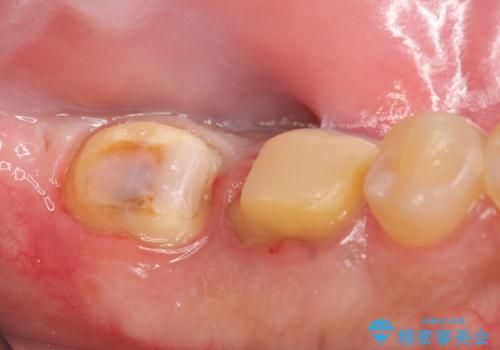

- 左下7の歯しみる、被せ物を被せてもすぐに外れてしまうといらっしゃった方の症例です。

左下に被せ物を被せるクリアランス(補綴のための上下のスペース)ないため、十分な歯冠長を確保するため歯冠長延長術を行いました。